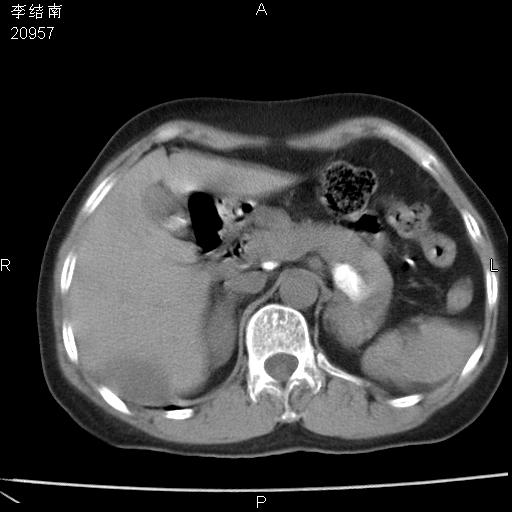

患者女,45岁,以右侧腰部包块来就诊,局部有压痛,皮肤颜色正常。因为是熟人扫的范围较大,患者有胆结石,胆源性胰腺炎病史。请大家看看,有手术病理。

可能大家觉得片子的质量不好,当时是做下腹部扫描,所以没有常规喝水,右腹壁的病灶当时是,密度不均有钙化影,局部骨质没见破坏,肝脏应该是受压的表现,所以当时考虑为腹壁的良性占位,各位老师考虑的神经源性肿瘤,我当时还真没想到,胰腺是胰腺炎治疗后改变.膈脚旁的混杂密度包快不好考虑什么,到上级医院做增强(腹部)+肺部平扫后,发现腹壁的病灶呈不均匀性强化局部可见囊性灶,当时考虑为腹壁结核,最具戏剧性的是膈脚旁的混杂密度灶确是胃的一部分,而腹壁的病灶确是脂肪瘤(简直不可思议)但是我亲眼所见在我们县医院开的.

很不好意思 ,患者后来手术切口裂开,临床医生作了病理证实是腹壁结核。

[病理诊断] CT13183腹壁结核!